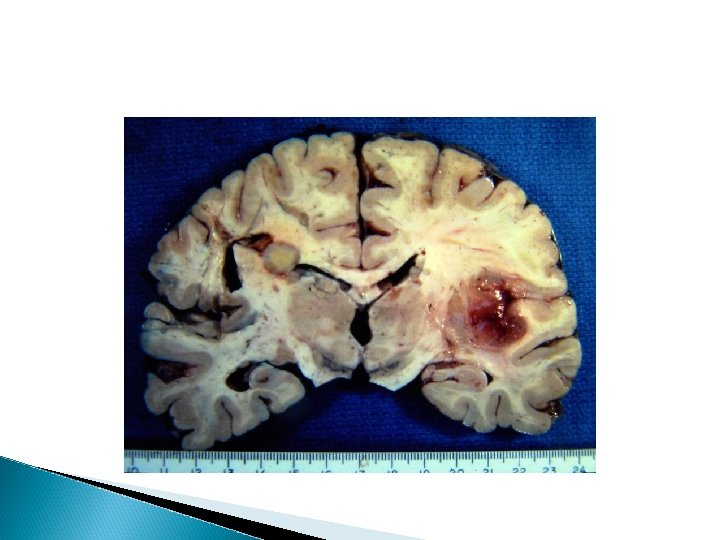

� Tuberculomas are conglomerate caseous foci within the substance of the brain, as shown in the image below. � Centrally located, active lesions may reach considerable size without producing meningitis. � Under conditions of poor host resistance, this process may result in focal areas of cerebritis or frank abscess formation, but the usual course is coalescence of caseous foci and fibrous encapsulation (ie, tuberculoma).